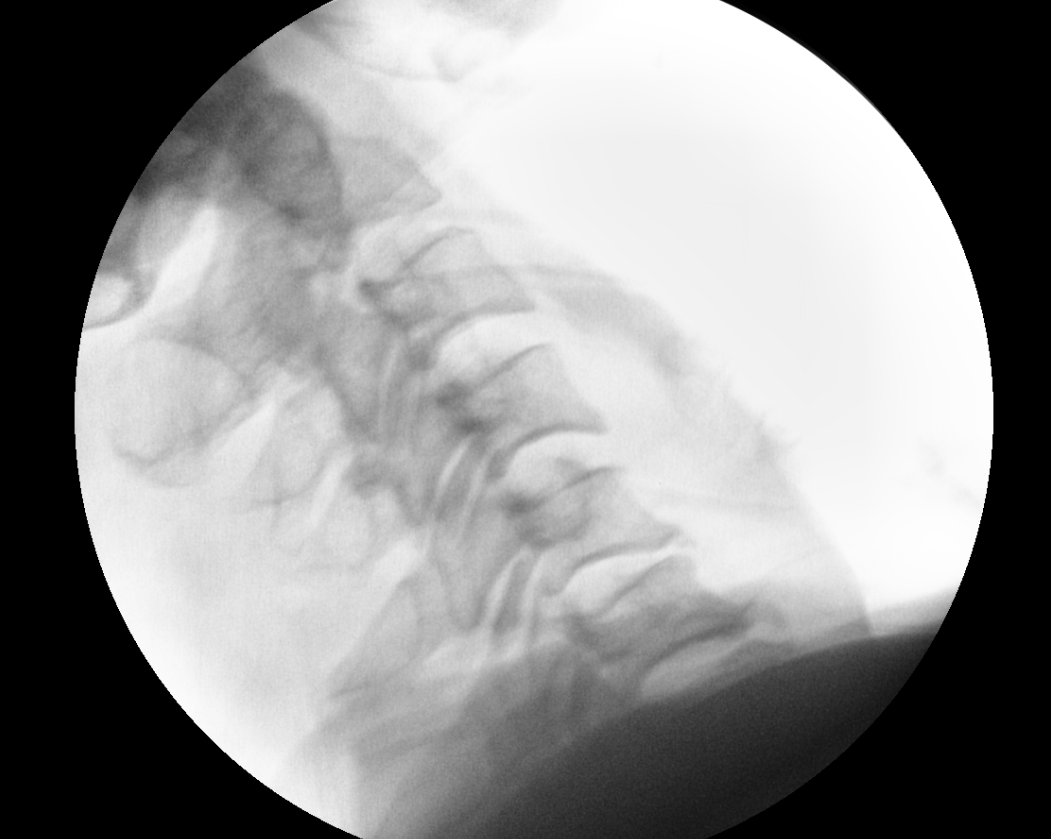

그 다음날에 점심정도에 다시 병원에 오셔서 수술 정하셨다고 하여, 수술방에 올라가 reduction 시행함

reduction 된 것을 확인 하였음.